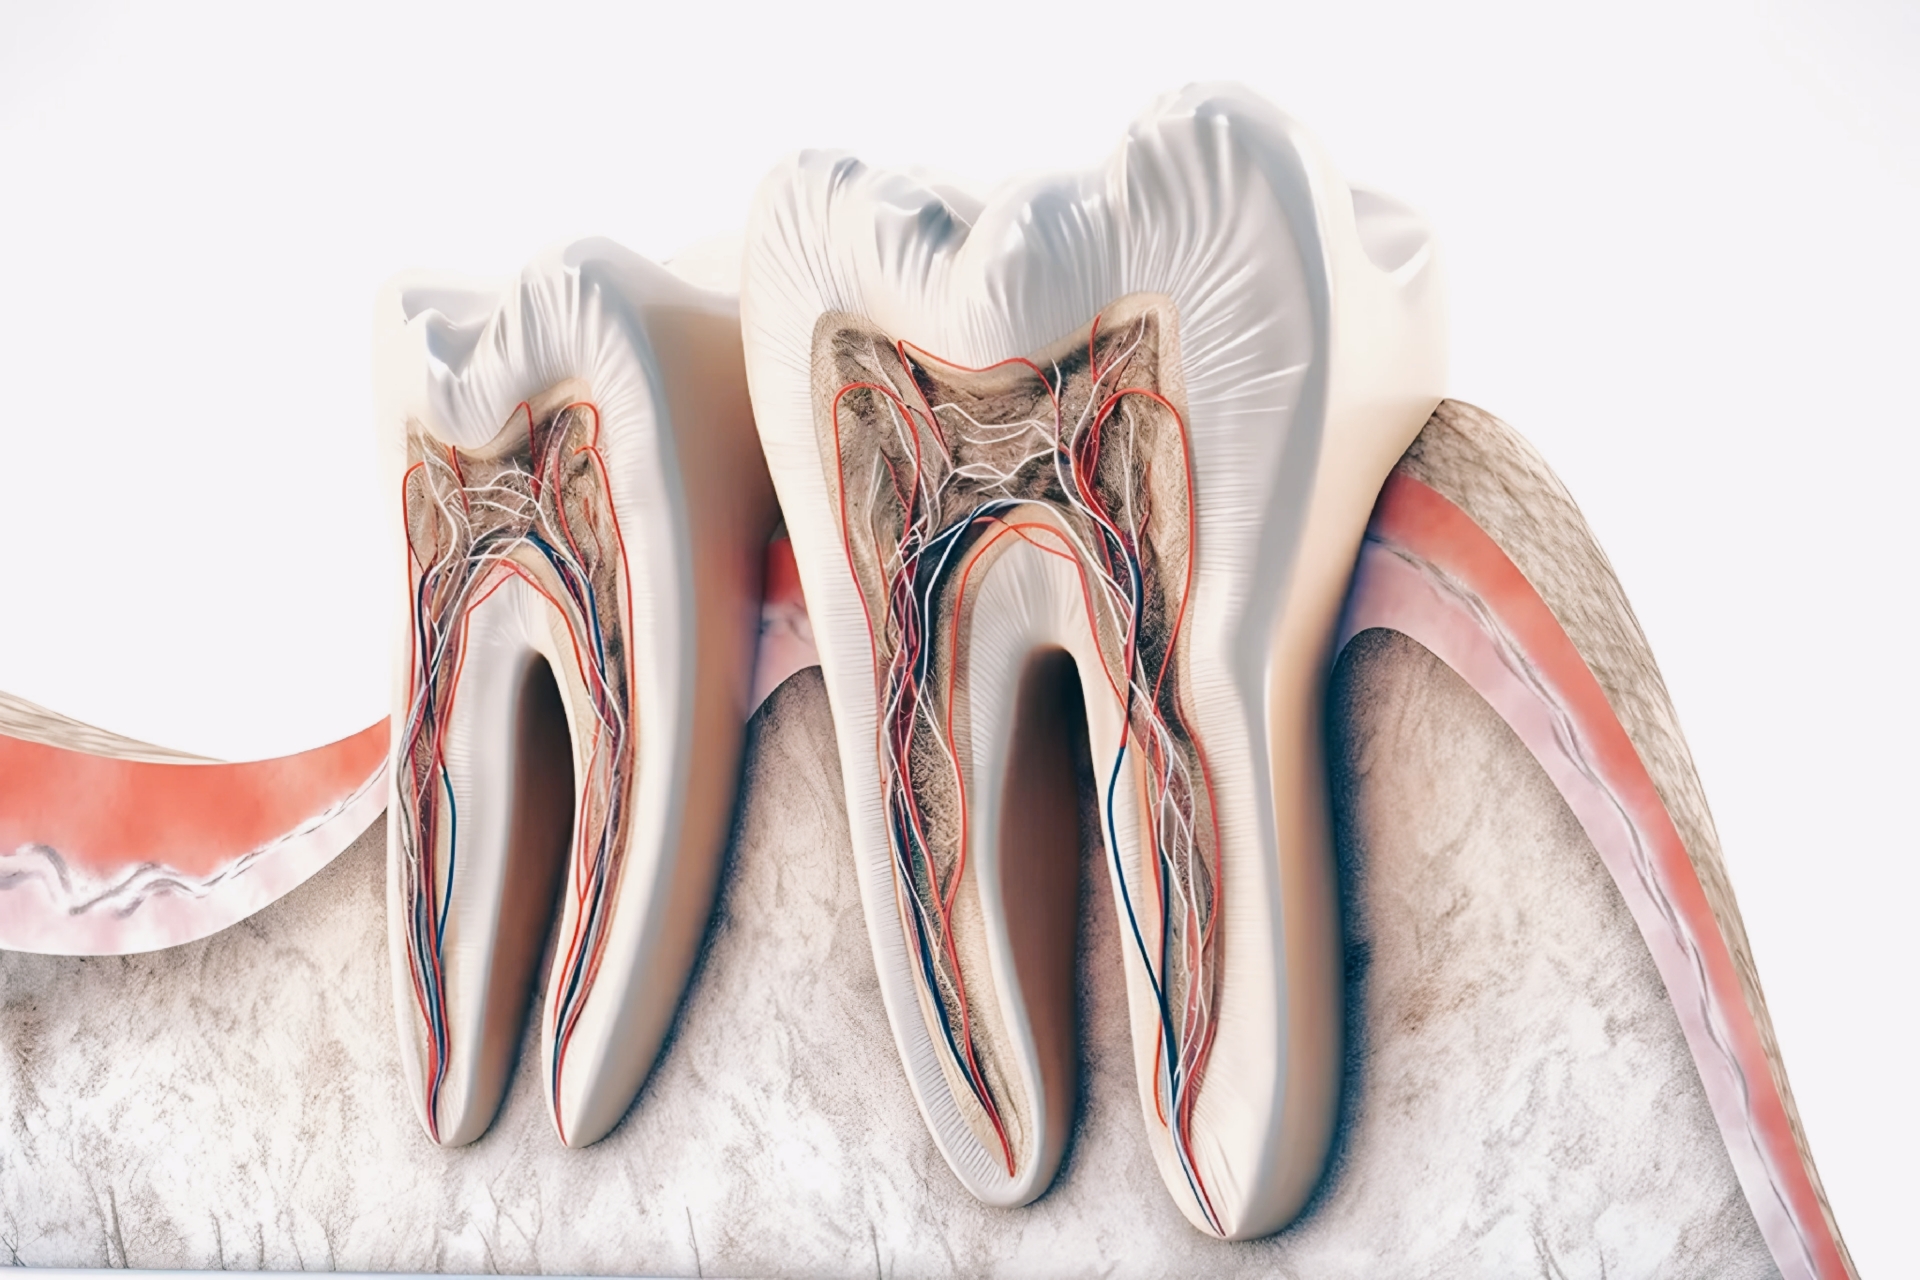

مغز دندان یا پالپ دندان (به زبان انگلیسی: Pulp) به رگها و اعصاب دندان می گویند. حفره مرکزی در تاج دندان، اتاق پالپ نامیده می شود. مجرای ریشه دندان را نیز کانال دندان نامیده می شود. در حالت عادی مغز دندان زنده و فعال است ولی پوسیدگیها و آزردگیهای رگها و عصبها باعث درد و سرانجام مرگ مغز دندان، و از بین رفتن مغز دندان می شود.